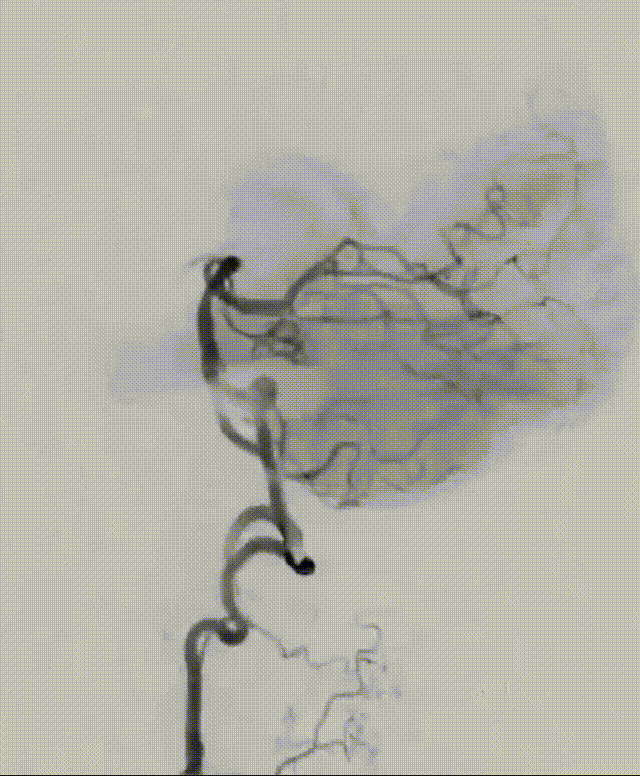

Tubridge Plus Case 2